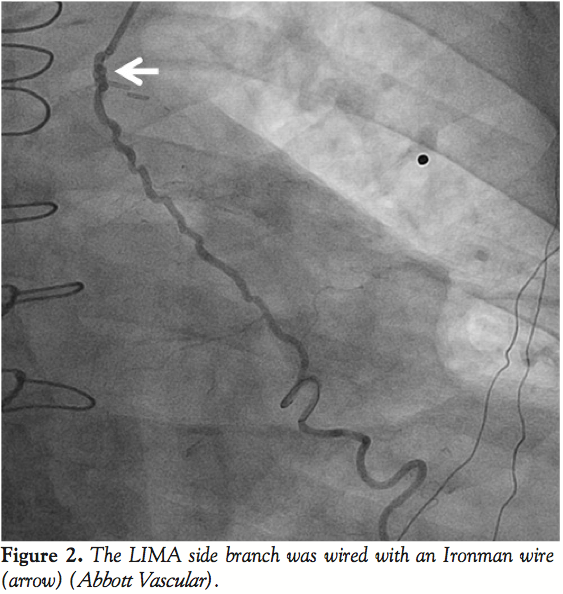

ABSTRACT: We present a case of angina in a patient with a left internal mammary artery graft that had a large side branch. Closure was attempted using an Amplatzer vascular plug but during attempts to position the device, the side-branch occluded, likely due to dissection, obviating the need for device deployment.

Left radial access was obtained with a 6 Fr sheath. The LIMA was wired with an Ironman wire (Abbott Vascular; Figure 2) and a Proxis catheter (St. Jude Medical) was inserted into the LIMA side branch (Figure 3). We attempted to deliver a 3 mm Amplatzer vascular plug (AGA Medical) through the Proxis catheter in the LIMA side branch, however significant resistance was encountered during delivery attempts. The device was partially deployed but in suboptimal location due to movement of the catheter during delivery. The vascular plug was recaptured and removed. LIMA angiography demonstrated side-branch occlusion. The LIMA side branch remained occluded after 15 minutes of observation. The patient had an uneventful recovery and has had no recurrent angina during 3 months of follow-up.